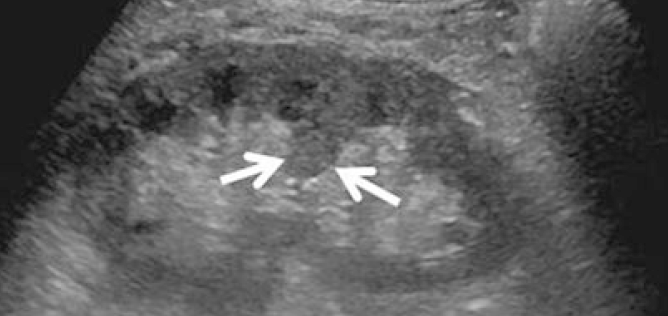

3-Duplex kidney

هذا مصطلح واسع يشمل عدة متغيرات منها وجود كليتين ملتصقات ببعض أو وجود two collecting systems في كلية واحدة. وهذه أيضا يوجد بها متغيرات أخرى من ناحية وجود حالب واحد أو حالبين ووجود شريان واحد أو اثنين.

يوجد هذا المتغير في قرابة ١٠٪ من الناس الطبيعيين. ويجب على الأخصائي التأكد من عدم توسع الحالبين وأيضا عدم وجود انسداد في أحد collecting systems وتحديدا العلوي.